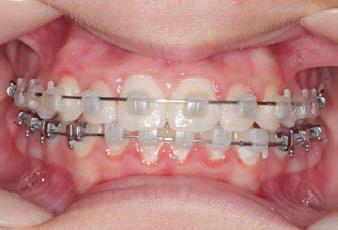

Carriere Motion 3D Appliance

Fastrack your orthodontic treatments. Save 6 months or more.

The SAGITTAL FIRST™ Philosophy is a time-tested approach that standardises, simplifies, and shortens Class II and Class III treatment times. It employs the Carriere Motion 3D Appliance to treat the AP dimension at the beginning of treatment before placing brackets or aligners. By resolving the most difficult part of treatment first, you can achieve a Class I platform in 3 to 6 months, shortening total treatment time by a minimum of 6 months1. You know how excited patients and parents become when you mention shorter treatment times.

CLASS II DIV.1 - Marra

PROVIDED BY: DR. LUIS CARRIÈRE

INITIAL - 4/4/18

PROGRESS 1 - 26/9/18 - Class I platform accomplished in 5.75 months with Motion 3D COLOR Appliance

PROGRESS 2 - 26/9/18 - Placement of the SLX 3D Clear Brackets

[CONTINUED ON NEXT PAGE]

with M-ONE .015 Cu Nitanium 27°

PROVIDED BY: DR. LUIS

PROGRESS 3 - 30/10/18 - With M-TWO .020 x .020 Cu Nitanium 35° archwire

PROGRESS 4 - 27/11/18 - 3 links power chain: 5, 4, bypass 3 to crimp hooks

PROGRESS 5 - 13/3/19 - With M-TWO .020 x .020 Cu Nitanium 35° archwire

PROGRESS 6 - 1/8/19 - With M-THREE.019 x .025 Beta Titanium wire

52 HENRY SCHEIN ORTHODONTICS

FINAL - 10/10/19 - Appliances removed AFTER

PROGRESS 7 - 10/10/19 - Final day in SLX 3D Clear Brackets BEFORE